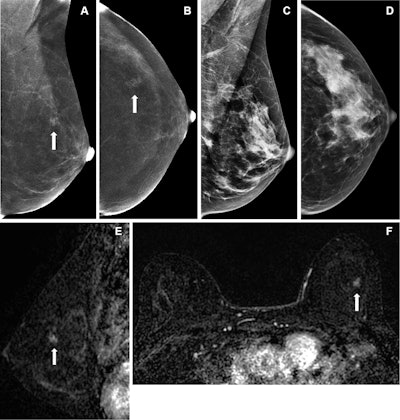

Images depict true-positive findings in a 51-year-old woman with a left breast focal nonmass enhancement. (A) Mediolateral oblique and (B) cranio-caudal contrast-enhanced mammographic (CEM) images show the enhancement (arrows). No correlate was identified on (C) mediolateral-oblique or (D) craniocaudal low-energy images, or whole-breast ultrasound (not shown). Contrast-enhanced breast MRI shows a suspicious enhancement on (E) sagittaland (F) axial subtraction images (arrows), correlating with the finding on CEM images. MRI-guided biopsy (not shown) showed flat epithelial atypia, withsubsequent surgery confirming ductal carcinoma in situ.Images depict true-positive findings in a 51-year-old woman with a left breast focal nonmass enhancement. (A) Mediolateral oblique and (B) cranio-caudal contrast-enhanced mammographic (CEM) images show the enhancement (arrows). No correlate was identified on (C) mediolateral-oblique or (D) craniocaudal low-energy images, or whole-breast ultrasound (not shown). Contrast-enhanced breast MRI shows a suspicious enhancement on (E) sagittaland (F) axial subtraction images (arrows), correlating with the finding on CEM images. MRI-guided biopsy (not shown) showed flat epithelial atypia, withsubsequent surgery confirming ductal carcinoma in situ.RSNA